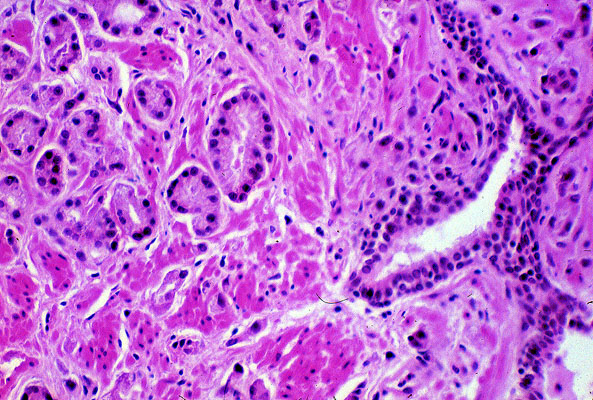

Adenocarcinoma, prostate, histology

The tumor is composed of small glands that are lined by a single layer of hyperchromatic cells. In contract to normal glands, which have two layers, these neoplastic glands have only one layer and abut directly onto the interstitial connective tissue. A normal prostatic duct appears at the far right.